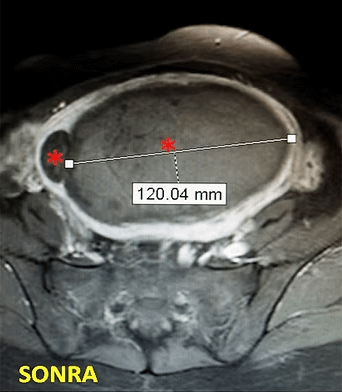

39 yaşında, kabızlık, gaz ve sık idrara çıkma şikayetleri var. Emar’da karını dolduran dev miyom (*) mevcut. Miyomektomi önerilmiş, ancak gerekirse rahimin alınabileceği söylenmiş. Embolizasyondan sonra dev miyom yanında bir başka küçük miyomun da öldüğü ve küçüldüğü izleniyor. 6 ay sonra hasta şikayeti kalmamıştır.